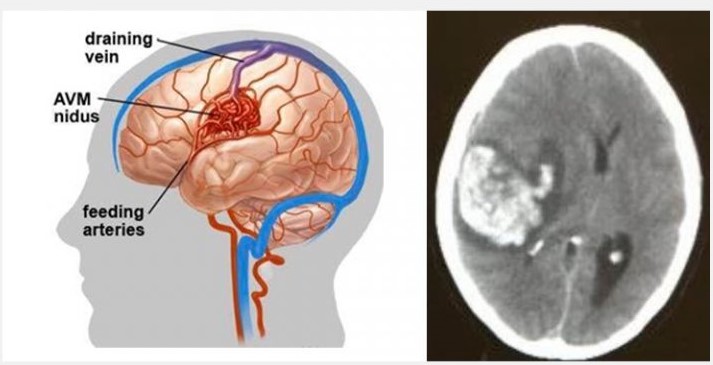

先天性的大腦動靜脈畸形血管瘤(Congenital Cerebral Arteriovenous Malformation)

一般人亦以為中風和年齡一定有關係,然而這是錯誤的,任何年齡即使是小孩也有機會中風。皆因中風是腦血管疾病所致,而我們每人無論任何年紀也有機會患上先天、或後天的腦血管疾病。小孩和少年的中風,可以是患有先天性的大腦動靜脈畸形血管 (Congenital Cerebral Arteriovenous Malformation) 所導致的出血性中風。

四歲小朋友,出生以來一切健康正常,沒有任何症狀,有一天隨著母親逛街,突然感到頭部劇痛,然後急速昏迷。送到醫院證實是先天性大腦動靜脈畸形血管瘤爆破而引致的嚴重出血性中風,他雖然從死亡鬼門關好不容易才被拯救出來,但即使經過多年的救治,也不能逆轉中風對大腦神經的永久損害,如今小孩仍然患有嚴重殘疾,不能與人溝通及需要長期臥床。

三個分別是十五、十六歲和三十九歲的女孩和女士,一向健康正常及沒有頭痛症狀,三個不約而同地分別在懷孕初期、中期及後期,突然嚴重大腦出血性中風,劇烈頭痛後急速昏迷休克,在緊急腦外科開顱手術清除瘀血及減低顱內壓後, 幸好兩名十五、十六歲的少女和他們的小孩得到完全的康復,沒有任何後遺症。可是39歲的女士,雖然其小孩能夠正常地活下來,但女士卻變成了植物人,在醫院臥床了五年後才去世。

兩位分別是16歲的少年和56歲的男士,在沒有任何徵象之下做了詳盡的身體檢查,三維立體腦血管造影顯示兩人的大腦都有先天性的腦血管動靜脈畸形,在專科醫生建議之下透過了一段時間的觀察和保守治療,其後利用了微創內血管治療加上放射治療,畸形血管得到了有效的根治,病人與生俱來的大腦炸彈得到了拆除,減低了他們將來出血性中風的可能性。